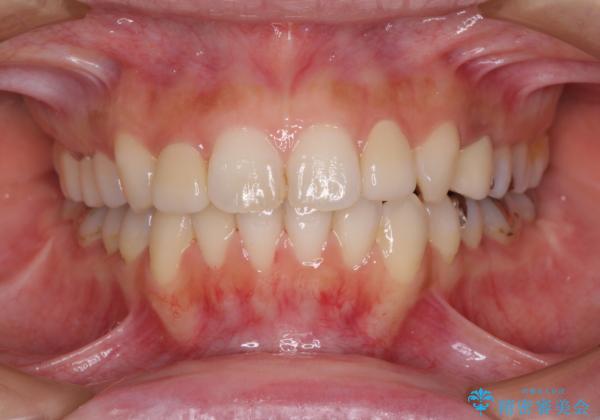

複数歯の補綴治療を行う場合、仮歯やセラミッククラウンを装着する度に保定装置を作り替える必要があり、その度に後戻りを起こす可能性が高くなります。

インビザラインであれば、矯正治療後半で補綴治療を行い、その後矯正治療を継続することでスムーズに治療を終えることができます。